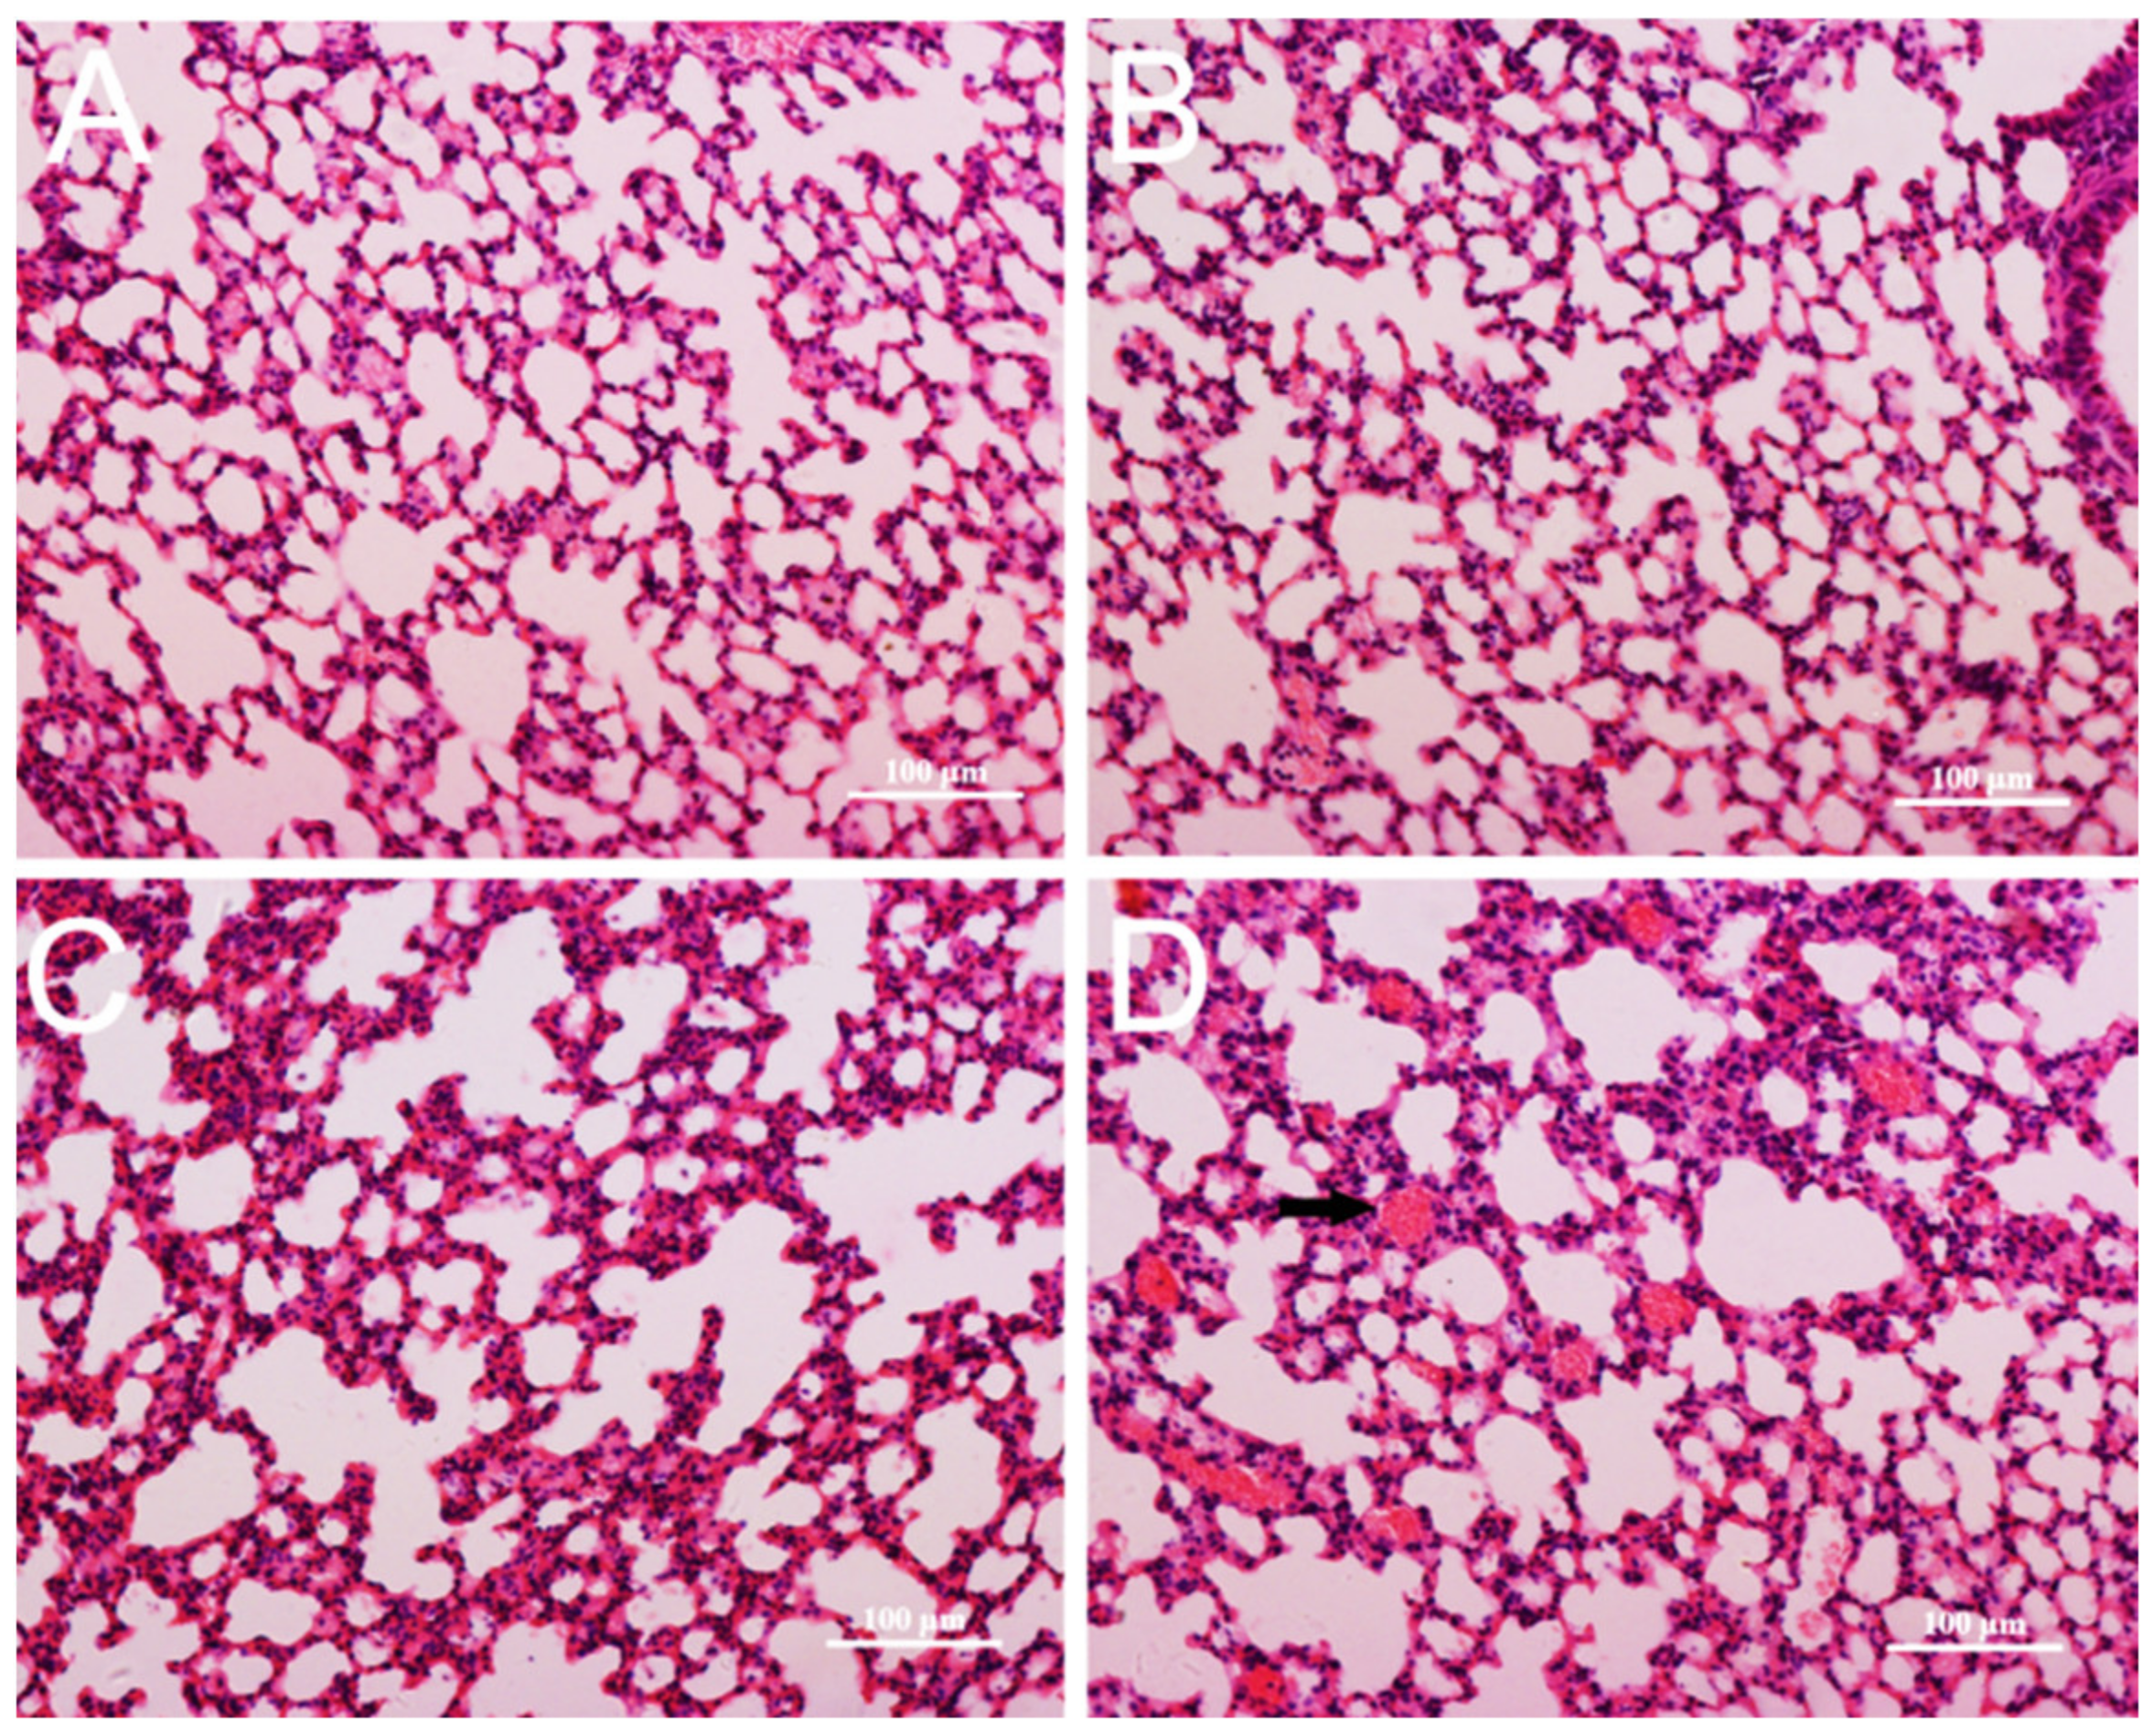

3.4. Pathological Changes in Mice